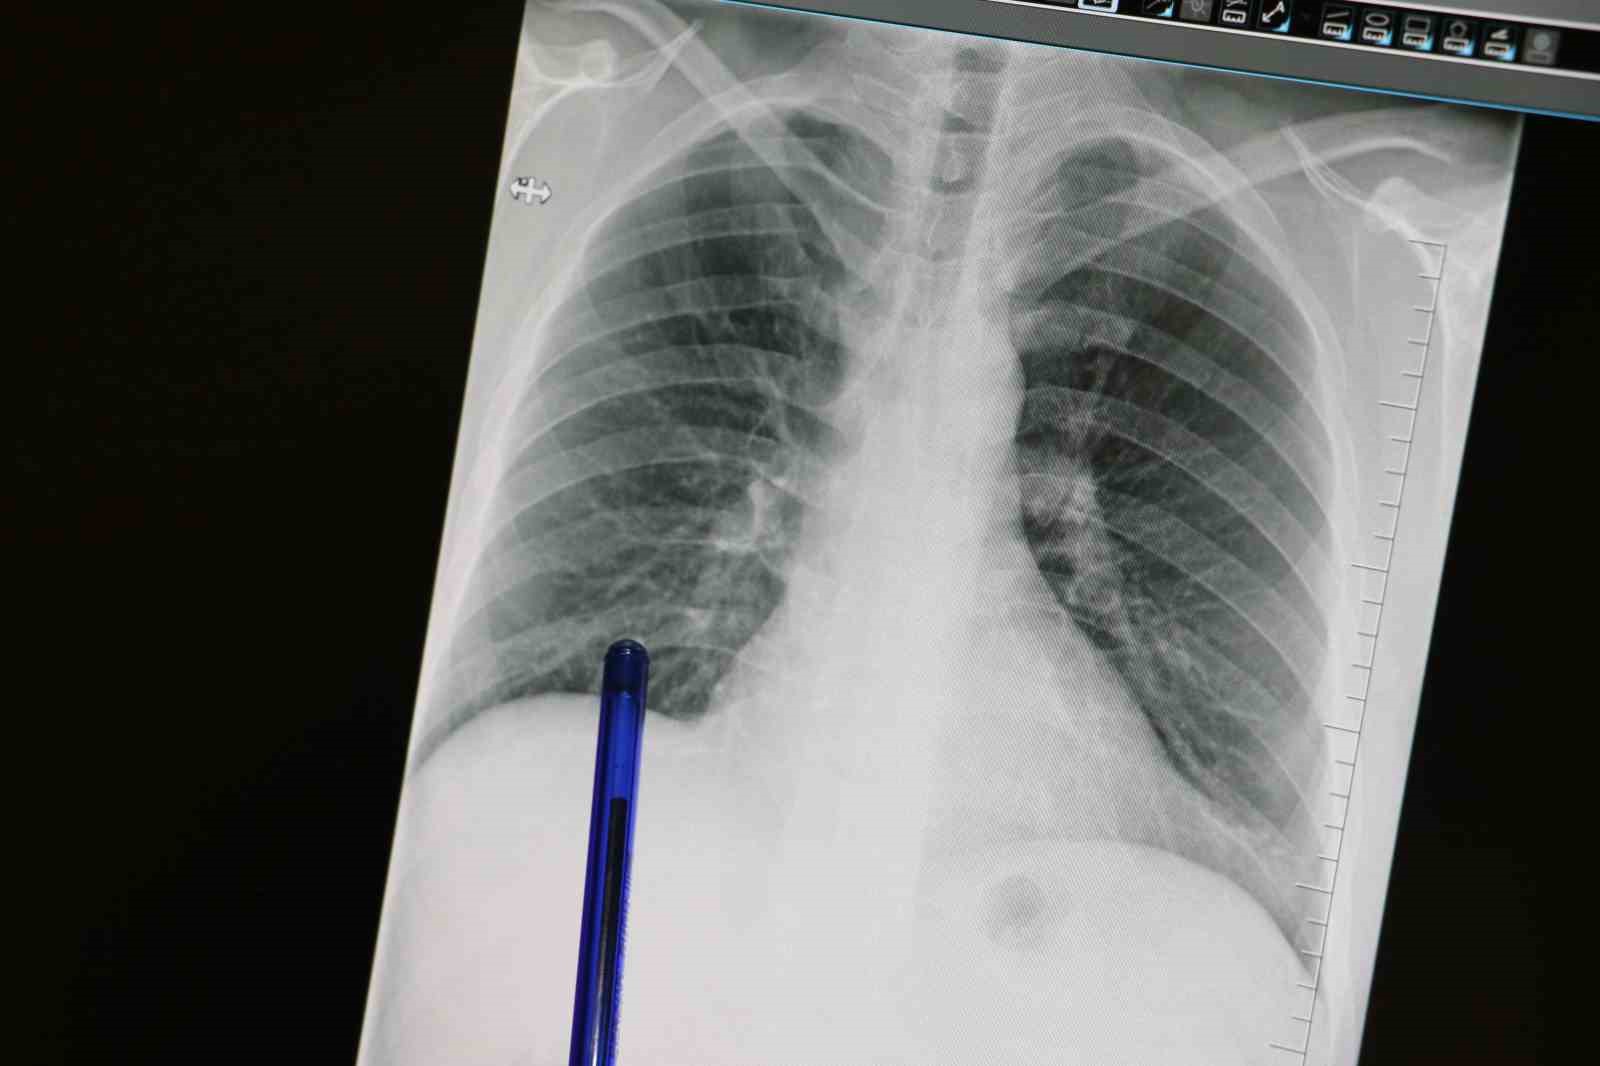

Kasım ayı, Türkiye’de akciğer kanserine dikkat çekmek ve erken tanının önemini vurgulamak amacıyla ‘Akciğer Kanseri Farkındalık Ayı’ olarak kabul ediliyor. Akciğer kanseri ise akciğer dokusundaki hücrelerin kontrolsüz çoğalmasıyla oluşan ve diğer organlara yayılabilen ciddi bir hastalık olarak biliniyor. Genellikle erken evrelerde belirti vermediği için geç fark ediliyor ve bu durumda tedavi şansını azaltıyor. En önemli risk faktörü sigara kullanımı olsa da, sigara içmeyen kişilerde de bu hastalık görülebiliyor. Pasif içicilik, hava kirliliği, genetik yatkınlık ve bazı kimyasal maddelere uzun süreli temas ileri yaşta akciğer kanseri riskini artıran diğer etkenler arasında bulunuyor. Konuya ilişkin açıklamalarda bulunan Medicana Sivas Hastanesi Göğüs Hastalıkları Uzmanı Dr. Büşra Yayla Yerlikaya, öksürük ve balgam çıkarma gibi basit görünen semptomların kanserin belirtisi olabileceğini söyleyerek, "Bu hastalık, hem dünyada hem de ülkemizde kansere bağlı ölümlerin en sık nedenidir. Ne yazık ki genellikle erken evrede belirti vermediği için geç tanı alabilmekte ve bu da tedavi şansının azalmasına sebep olabilmektedir" dedi.

Özellikle sigara içen bireyde öksürük gibi belirtiler varsa bir uzman tarafından değerlendirilmesi gerektiğini belirten, "Akciğer kanserinin en sık belirtileri ise uzun süren öksürük, balgamda kan, nefes darlığı, kilo kaybı ve göğüs ağrısıdır. Özellikle sigara içen birinde yeni başlayan ya da karakteri değişen öksürük varsa mutlaka bir göğüs hastalıkları uzmanı tarafından değerlendirilmelidir. Erken tanı her kanser türünde olduğu gibi akciğer kanserinde de hayat kurtarır. 50 yaş üzeri ve uzun süre özellikle 20 paket yıl ve daha fazla sigara içmiş kişilerde düşük doz tomografi ile tarama yapılması, hastalığın erken evrede erken tanı sağlar ve tedavi şansını ciddi şekilde artırır. Sigarayı bırakmak her yaşta faydalıdır. Bıraktıktan sonraki on yıl içinde akciğer kanseri riski büyük oranda azalır. Çalışmalar 10 yıl sonra yüzde 50, 15 yıl sonra ise yüzde 90’a kadar akciğer kanseri riskinin azaldığını göstermiştir. Sigara içen bireylerde sabahları balgam ve öksürükler mevcut oluyor. Bu durumlarda balgamın karakter değiştirmesi ve artması önemli bir belirti olabiliyor" diye konuştu.